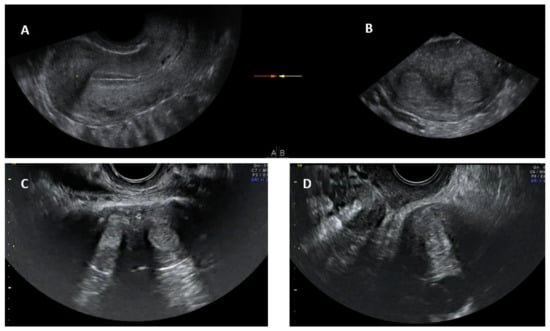

4.2. 2D Transvaginal Ultrasound

Conventional transvaginal ultrasound is minimally invasive and a less expensive way of assessing uterine morphology and ruling out uterine anomalies [13]. Ultrasound evaluation can be timed in the secretory (luteal) phase of the menstrual cycle as the endometrium, being bright and echogenic, is easy to visualise; ultrasound is therefore more appropriate for evaluating the uterus for congenital anomalies. The visualisation of a double endometrial complex on a transverse plane points towards a uterine anomaly (Figure 4) and the differential diagnosis would be a bicornuate, septate, subseptate or arcuate uterus. However, 3D ultrasound facilitates simultaneous visualization of both the external (serosal surface) and internal (endometrial) contours of the uterine fundus through its unique feature of providing the coronal plane of the uterus and can correctly classify the uterine anomaly into a bicornuate, septate or subseptate, or arcuate uterus [14].

Systematic scanning through the longitudinal plane of the uterus may reveal a uterine complex that then disappears while moving to the opposite side, followed by the appearance of a second uterine complex, suggesting that the uterus may be a partial or complete bicorporeal uterus (bicornuate or didelphys). The transverse plane provides more information and widely placed double endometrial echoes, especially at the upper portion of the uterus towards the fundus (Figure 4C), and an indentation at the fundus on an oblique plane (if obtainable) are typical of a bicornuate uterus. The double endometrial echoes will be closer in a septate uterus (Figure 4B) in contrast to that in a bicornuate uterus. The distance between the serosal surface and the upper border of the endometrial echo in a longitudinal plane may also give a clue to distinguish between septate and bicornuate uterus, although not confirmatory. In uterus didelphys, the two whole uterine body with endometrial echoes will be separate to each other and placed apart (Figure 4D), and the clinical demonstration of two cervices confirm the diagnosis. Two uterine horns may be symmetrical or asymmetrical and two separate vaginas may be seen on speculum examination.

Figure 4. Longitudinal section of subseptate uterus in midsagittal plane (A); transverse plane of a subseptate uterus showing two endometrial echoes (B); transverse plane of a bicornuate uterus showing two endometrial echoes (C); transverse plane of uterus didelphys showing two uterine bodies (D).